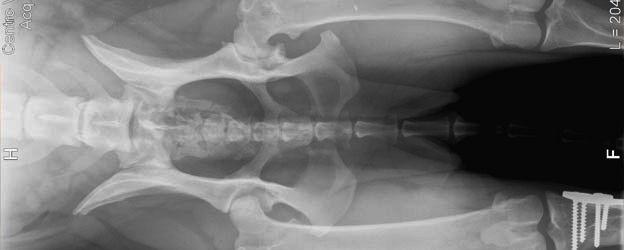

PA con displasia leve de cadera.